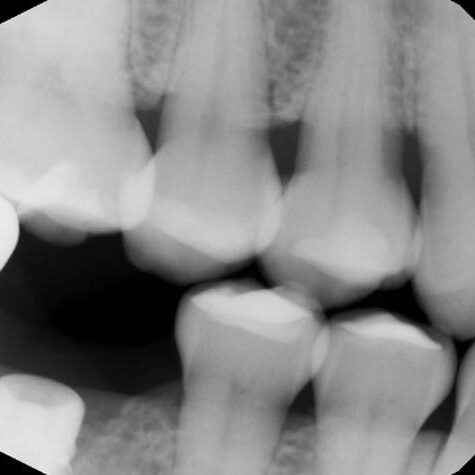

ULTRASONICS: Complications of Abutment Screw Retrieval Secondary to Prior Ultrasonic Attempts

There has been much written on the use of ultrasonics in retrieving fractured screw fragments, which I didn’t think a lot about until May of 2023, as it has not been a part of my fractured screw retrieval algorithm.